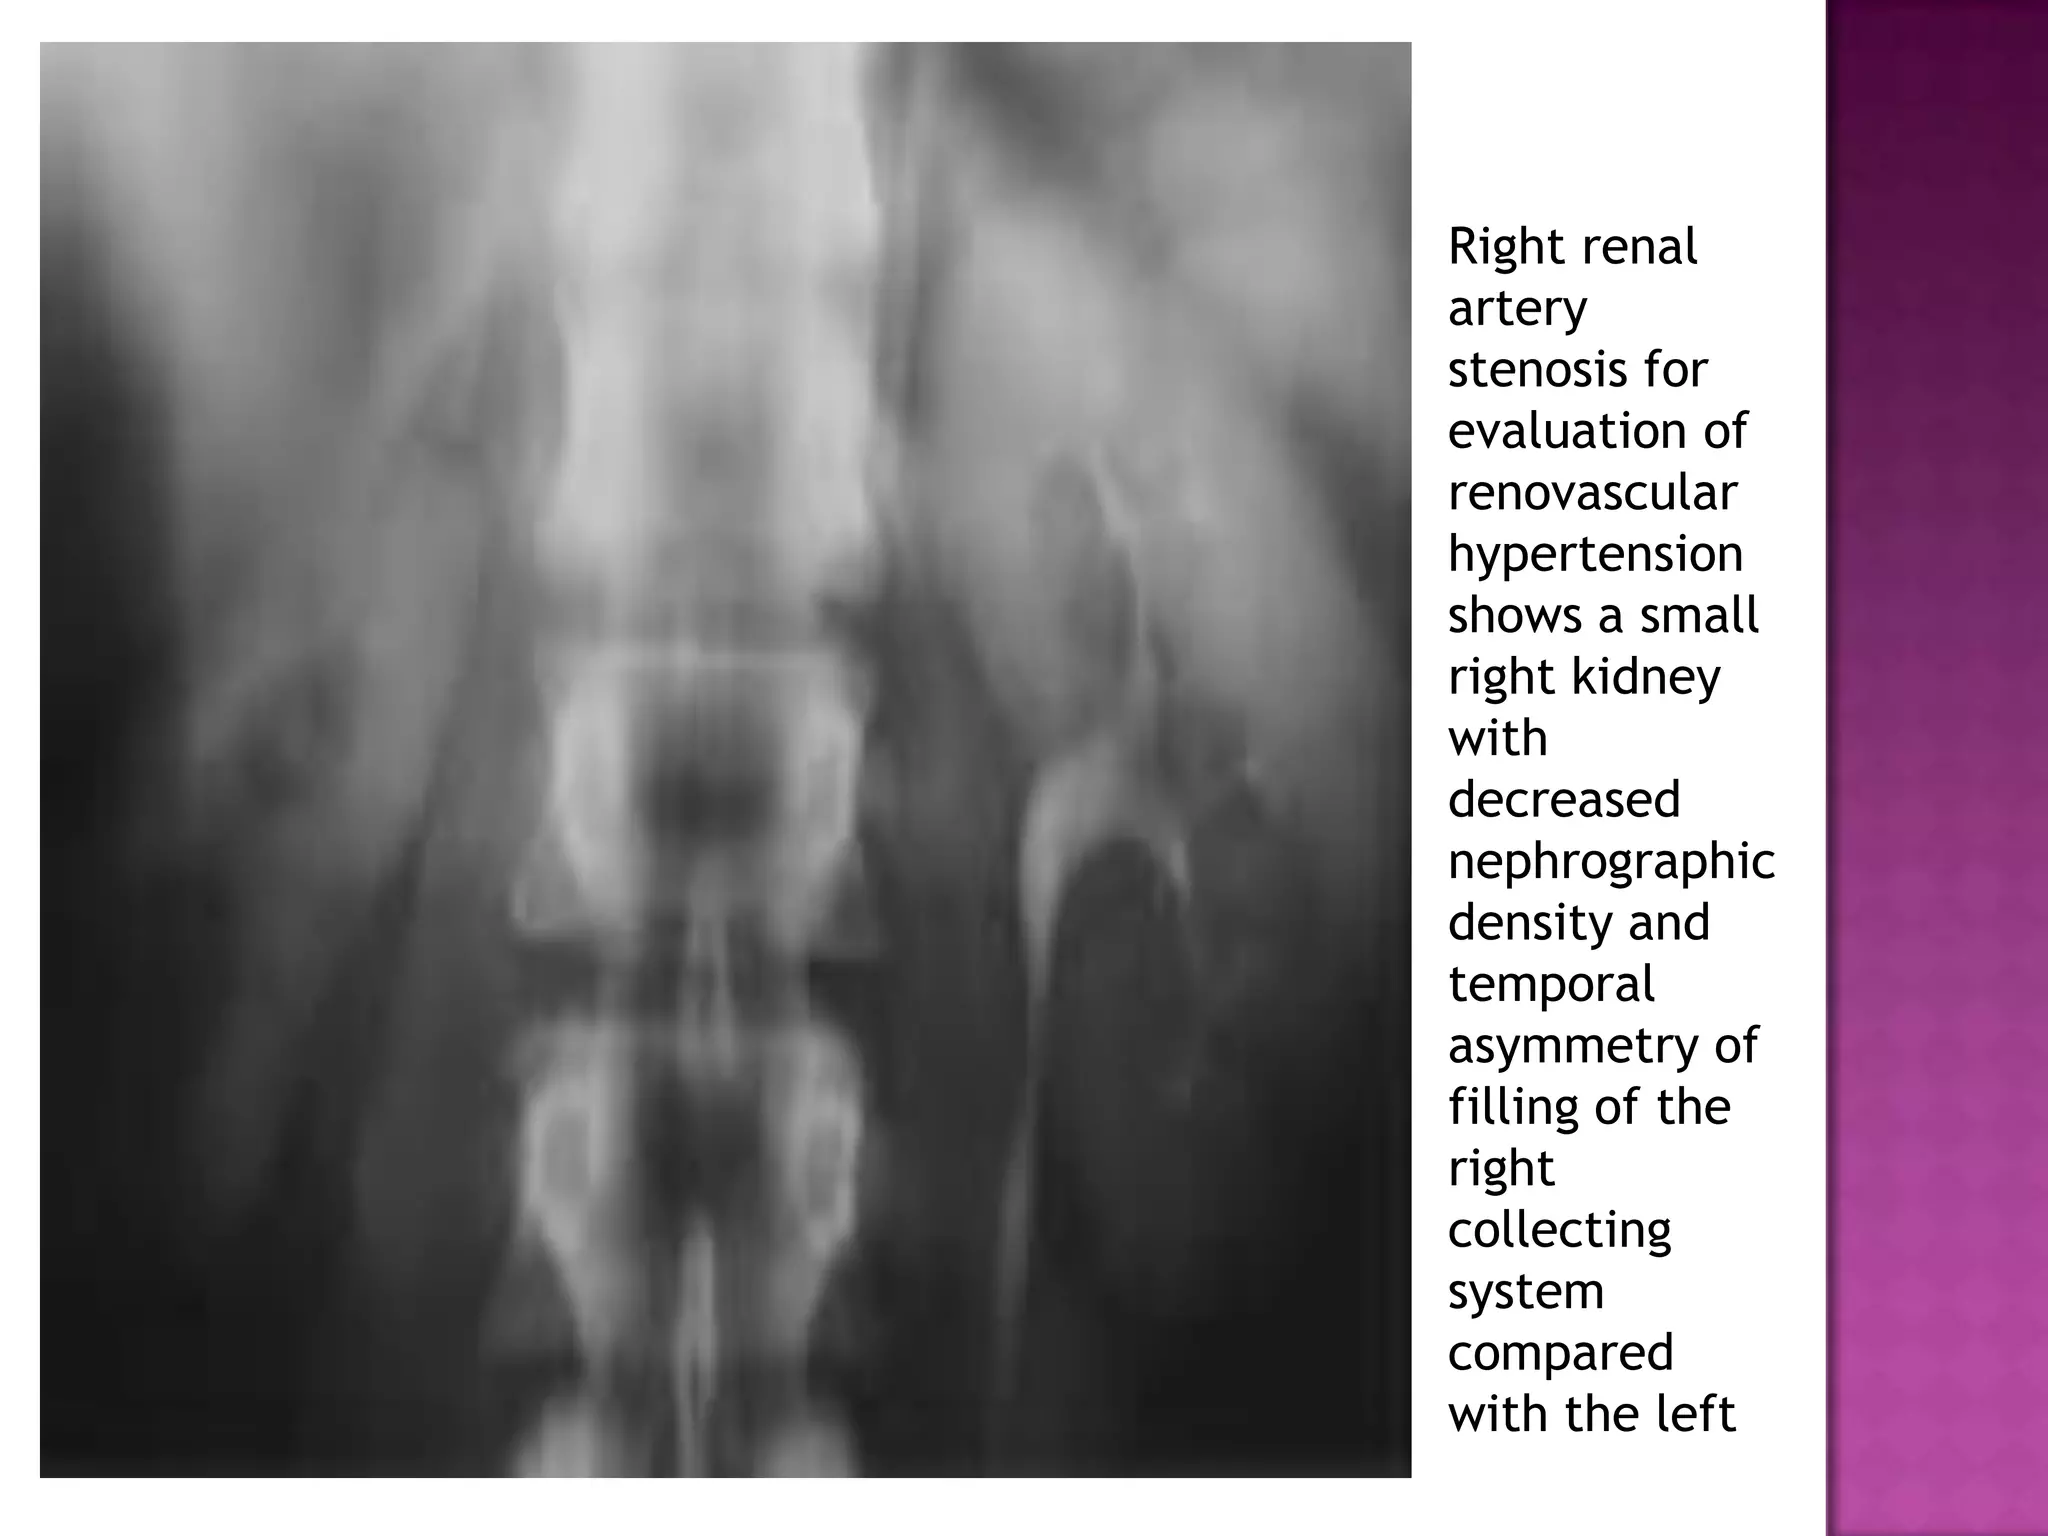

Right renal

artery

stenosis for

evaluation of

renovascular

hypertension

shows a small

right kidney

with

decreased

nephrographic

density and

temporal

asymmetry of

filling of the

right

collecting

system

compared

with the left

• 49.

Right renal artery stenosis for evaluationof renovascular hypertension shows a small right kidney with decreased nephrographic density and temporal asymmetry of filling of the right collecting system compared with the left

Fifteen-minute urographic image helps confirm the asymmetric renalsize. Note the hyperconcentra tion of contrast material in the right collecting system compared with the left.